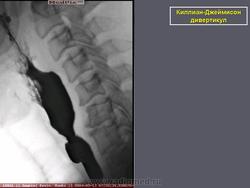

Киллиан – Джеймисон - дивертикул

Киллиан – Джеймисон - дивертикул.